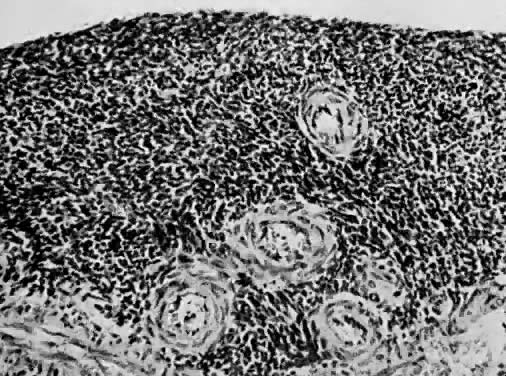

Numerous authors have reported that endometrial stromal myosis occurs predominately in premenopausal women.39,40,41 Bard and Zuna reported an average age of 42 years.40 Endolymphatic stromal myosis is composed of nodules of stromal cells with rounded nuclei and dense cytoplasm (Fig. 6). These tumors have frequently been confused with endometrial stromal sarcoma. The determination of the number of mitotic figures per 10 HPF is important in separating these two tumors. Endolymphatic stromal myoses have fewer than five mitotic figures per 10 HPF, and they have pushing rather than infiltrating margins (Fig. 7). Although these tumors have an innocuous appearance and prolonged clinical course, they can be fatal. The 5-year survival reportedly ranges from 66% to 100%.19,34,40 Some of these tumors reportedly contain estrogen and progesterone receptors.41,42 This may be the reason why some of them are sensitive to progesterone therapy. Bard and Zuna reported that nearly 40% of their Stage 1 endometrial stromal myosis (low grade) eventually recurs in the pelvis, abdominal cavity, and lungs. These recurrences may manifest themselves years after primary therapy.39,43,44

Fig. 6. Cellular detail of endolymphatic stromal myosis. The cells are uniform. There is minimal cellular atypia and no mitosis (H&E, × 350)

Fig. 7. Endolymphatic stromal myosis showing pushing margin (H&E, × 90)